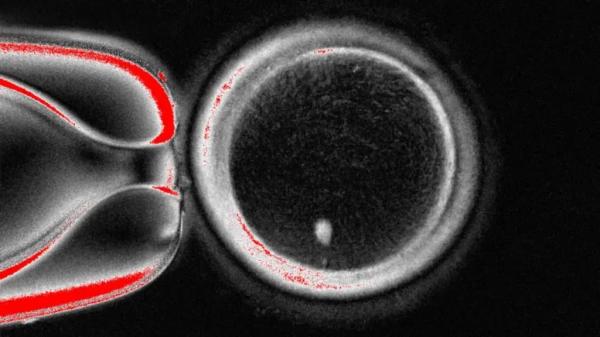

До сих пор репродуктивная медицина ограничивалась оплодотворением женской яйцеклетки мужской спермой, в результате чего появлялся эмбрион, из которого развивался ребёнок. Теперь учёные меняют правила. Они выделили из кожи клетку, содержащую весь генетический код человека, и поместили её в донорскую яйцеклетку, из которой удалили предварительно генетический материал.

Аналогичная технология была использована в 1996 году для создания первого клонированного млекопитающего – овечки Долли.